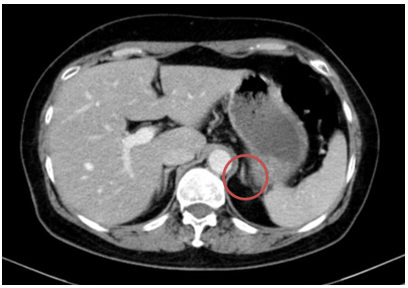

-  Chụp cắt lớp vi tính bụng: Theo dõi dày khu trú tuyến thượng thận trái tạo nốt đường kính khoảng 9mm

Hình 3. Hình ảnh chụp CT bụng trước điều trị: Nốt tuyến thượng thận trái

- Chụp cắt lớp vi tính bụng: Theo dõi dày khu trú tuyến thượng thận trái tạo nốt đường kính khoảng 9mm (không thay đổi)

Hình 10. Hình ảnh chụp CT bụng sau điều trị: Nốt tuyến thượng thận trái

- Theo dõi đánh giá đáp ứng bằng cắt lớp vi tính ngực, bụng định kỳ, theo dõi sát tổn thương tuyến thượng thận.